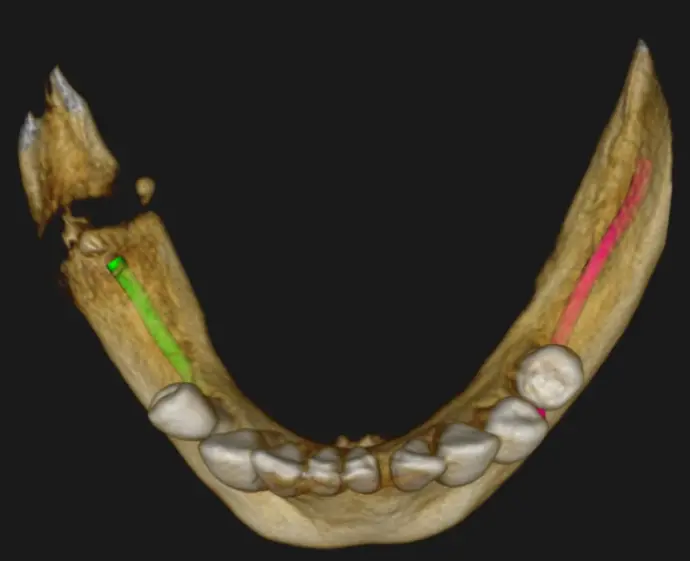

Tanto en la radiografía panorámica (imagen 1) como la tomografía maxilar inferior se puede observar una fractura mandibular a la altura del Angulo de la mandíbula con resto de fragmento óseo. (Fx Conminutas) Como también se logra ver todavía resto radicular de pieza dentaria. Ver imágenes 2 a imagen 5.

Para mayor información detallada se procedió a realizar una tomografía Cone Beam que abarque mas la zona de interés: zona Rama y Angulo de la mandíbula. Ver imágenes 6 a imagen 9.